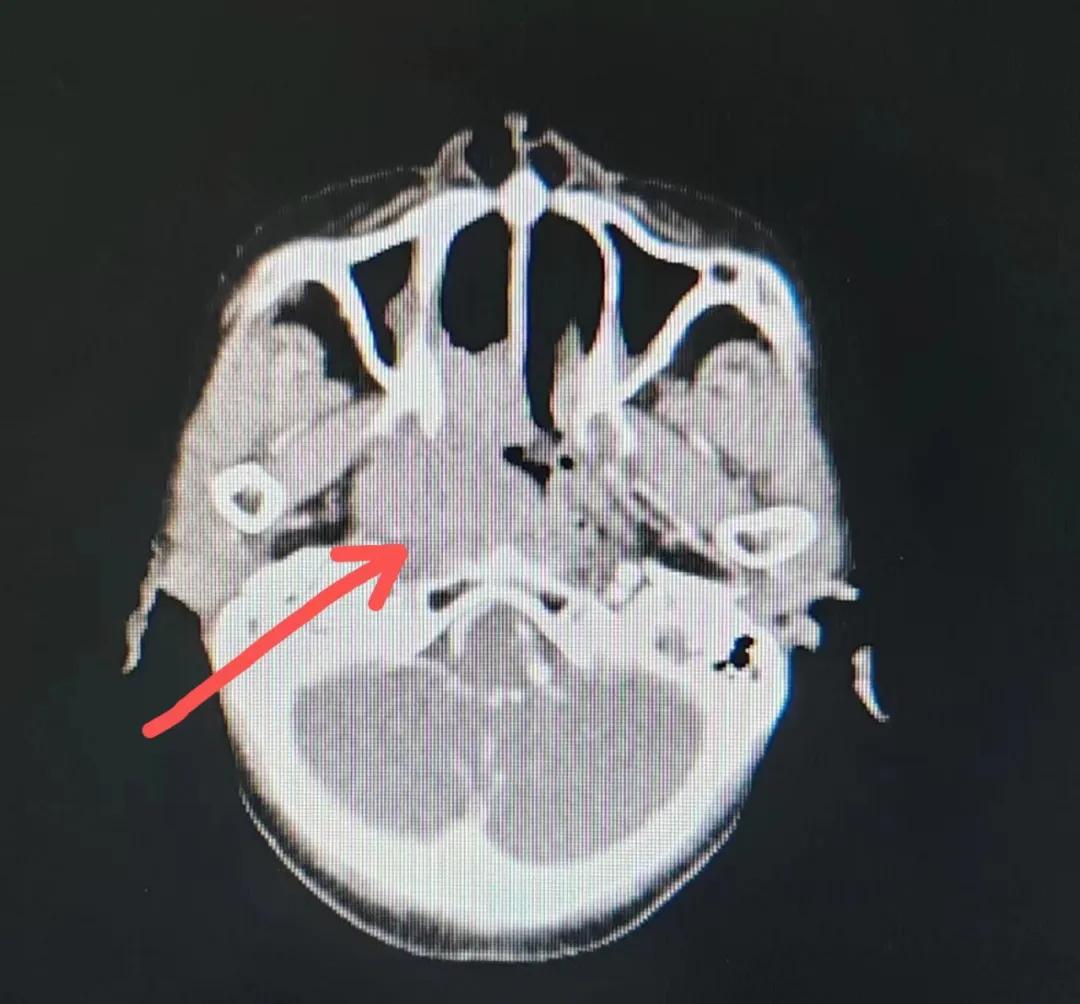

漯河市二院精準(zhǔn)放療救治七旬鼻腔惡性淋巴瘤老人

70歲的彭阿姨,5個(gè)月前因鼻部瘙癢伴流血不止在當(dāng)?shù)卦\所治療,瘙癢和出血癥狀不但沒有得到有效控制,反而進(jìn)行性加重,并出現(xiàn)鼻腔堵塞、進(jìn)食困難,經(jīng)外院病理活檢確診為“鼻腔惡性淋巴瘤”。不斷加重的病痛已嚴(yán)重影響了老人的生活質(zhì)量,為求診治,患者及家屬于今年2月份慕名來到了市二院放療科。

治療前

老人因鼻部腫物堵塞鼻腔并且侵犯鼻咽導(dǎo)致鼻塞、疼痛、吞咽困難,身心都備受煎熬,趙亮主任在詢問其病史期間幾度落淚。趙亮主任向患者及家屬解釋說:“現(xiàn)代放療比過去的傳統(tǒng)放療設(shè)備先進(jìn),技術(shù)不斷提升,能對(duì)腫瘤區(qū)域的照射劑量進(jìn)行優(yōu)化,做到準(zhǔn)確定位、精準(zhǔn)照射,同時(shí),最大限度地降低正常組織的受量,對(duì)全身情況影響很小。”

考慮到患者年齡較大、體質(zhì)差,手術(shù)難度大,且常規(guī)的放射治療難以保護(hù)患者晶體造成患者雙眼視力損傷,放療團(tuán)隊(duì)以最快的速度制定了精準(zhǔn)放射治療方案并開始為其實(shí)施治療。僅僅數(shù)日后,老人腫塊出血即得到控制,腫塊明顯縮小,放療20次后腫塊迅速縮?。?/div>

治療后

放療結(jié)束,除了放療處的皮膚輕微放射性皮炎外,基本沒有什么不良反應(yīng)。復(fù)查發(fā)現(xiàn),鼻腔淋巴瘤已不可見,目前患者已康復(fù)出院。